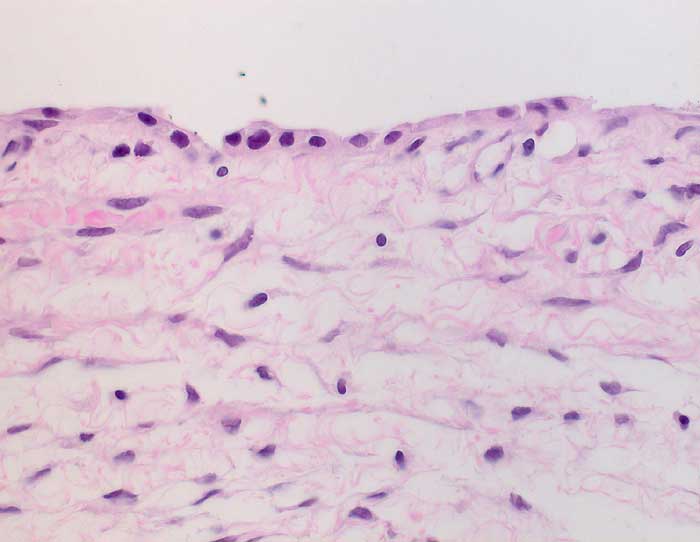

PathoPic ID 6251 - Seröses Zystadenom des Ovars

Seröses Zystadenom des Ovars

benigner Tumor

Ovar

Fibrosierter Zystenbalg ausgekleidet von einem einschichtigen kubischen Epithel mit kleinen runden Kernen ohne Atypien. Der Epithelbelag fehlt stellenweise.

6cm grosse Ovarialzyste.

Histologie

400